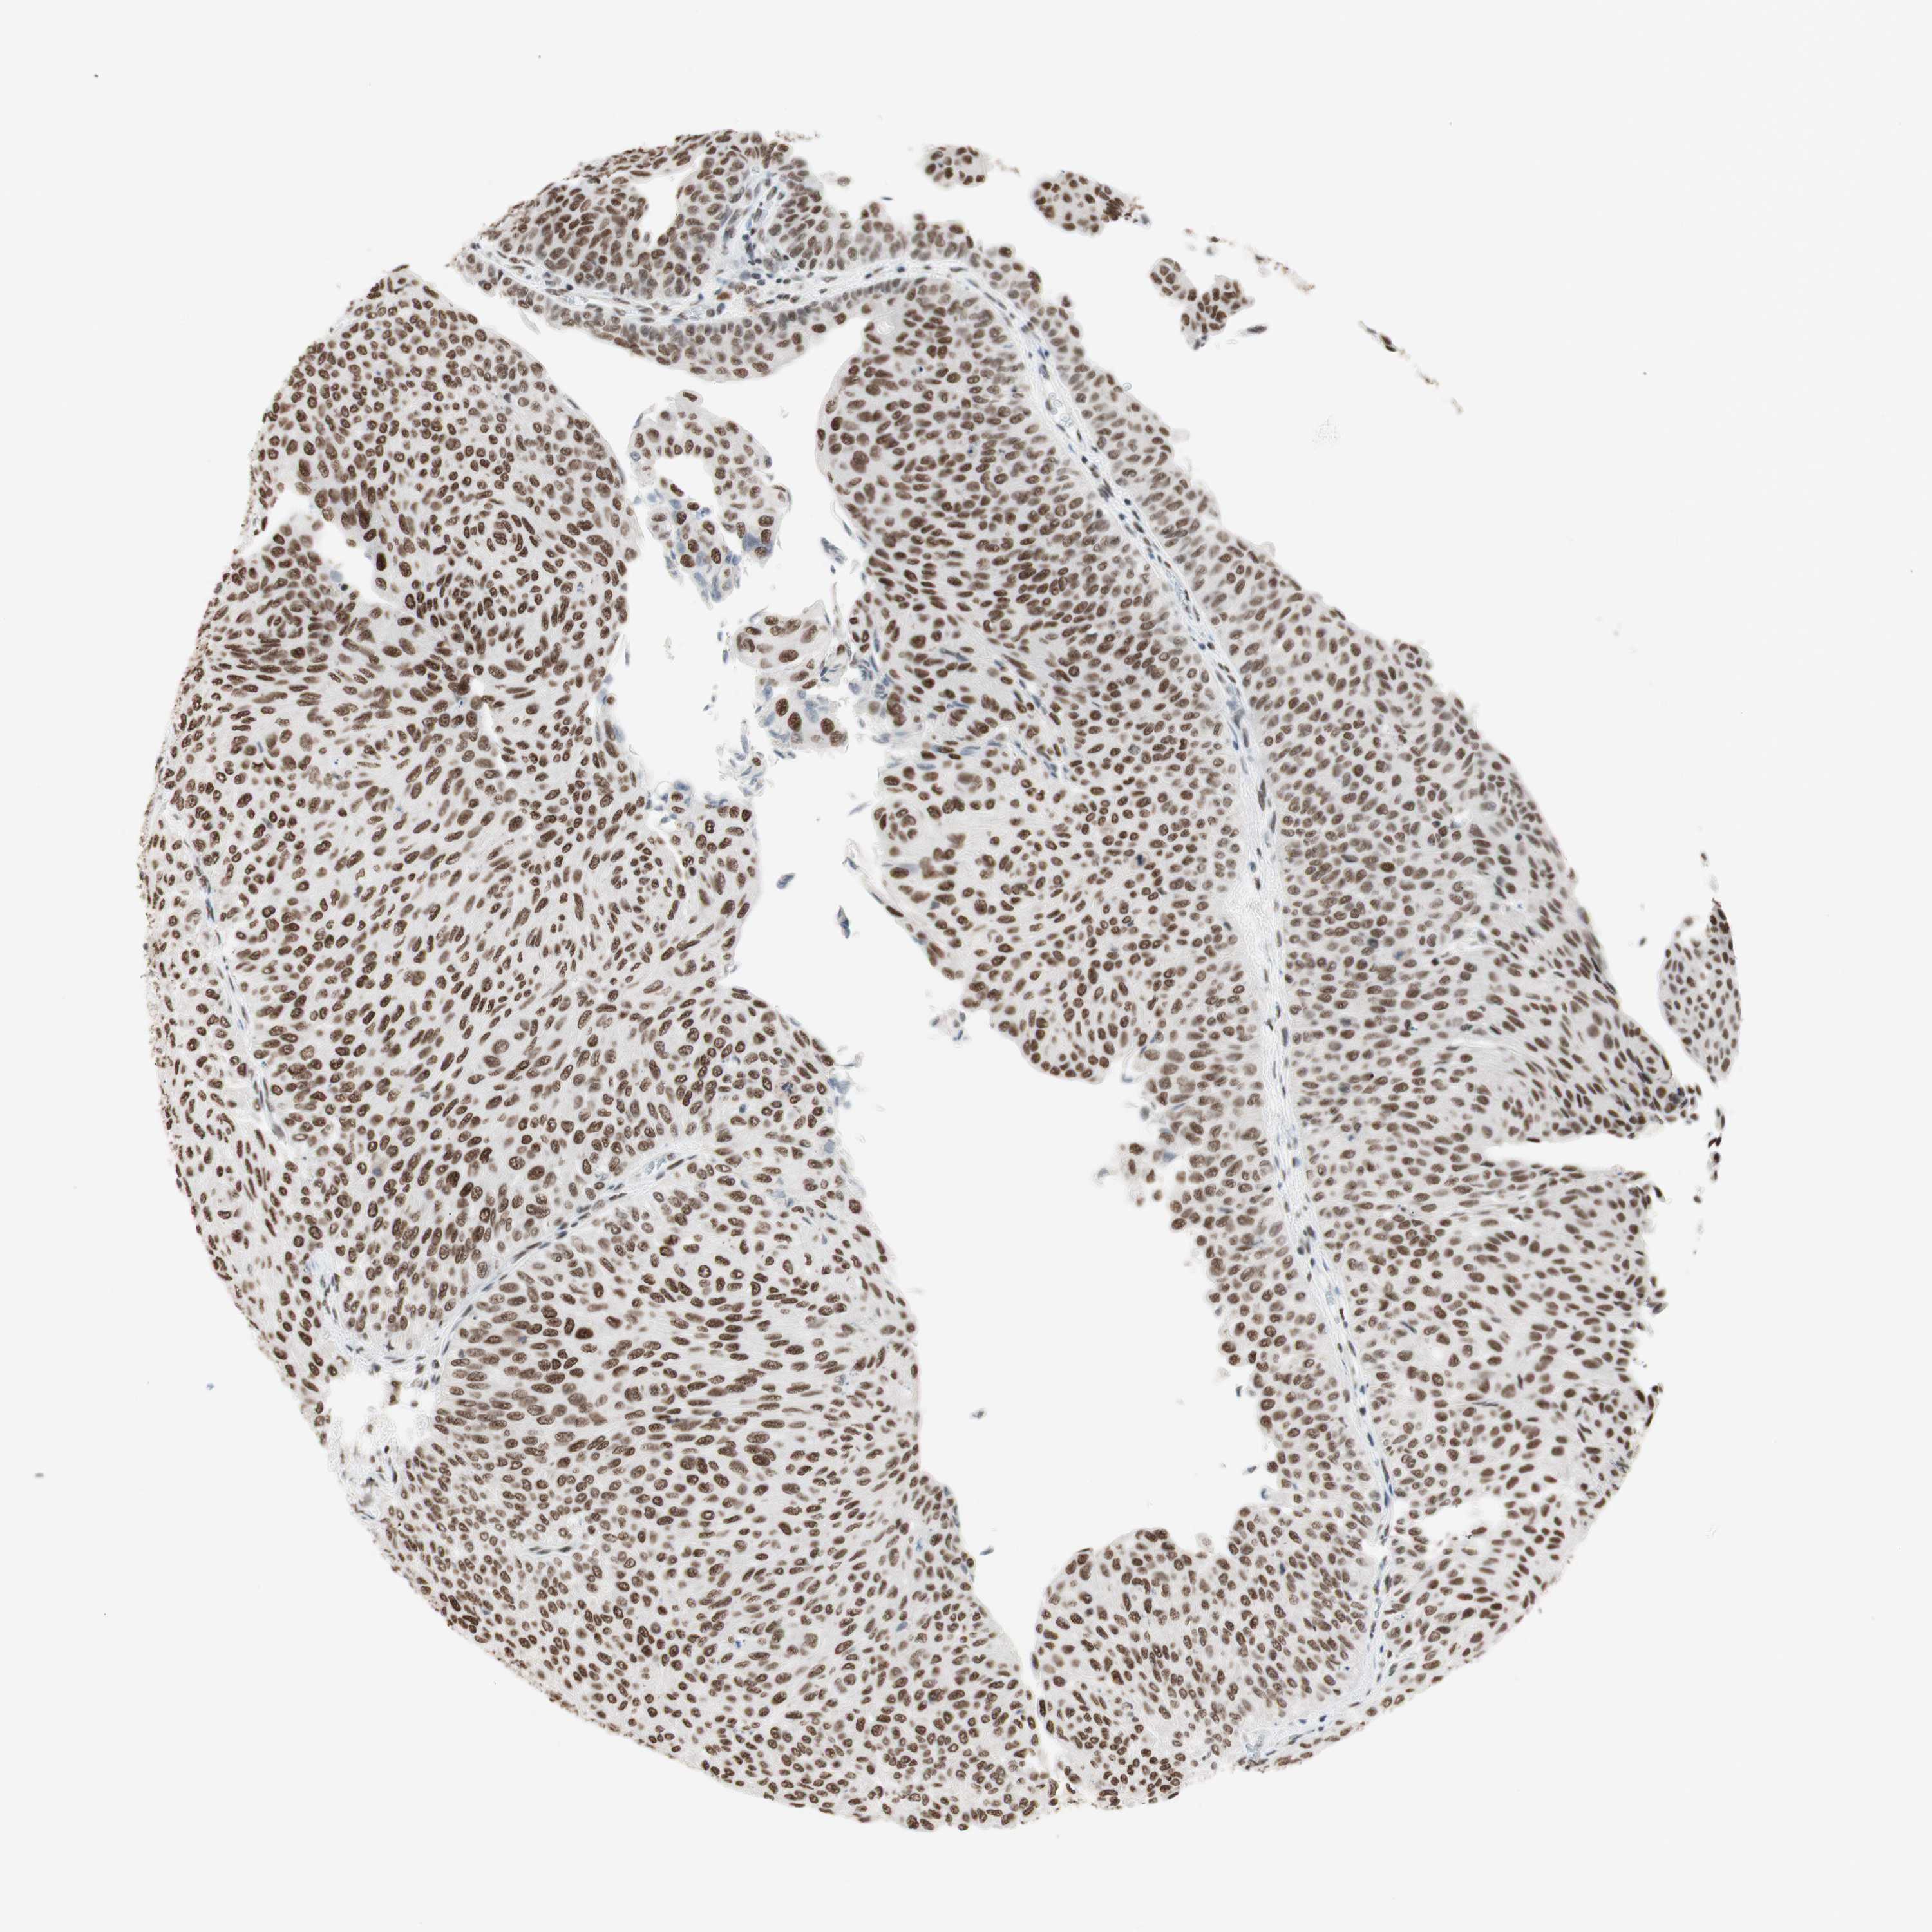

UROTHELIAL CANCER - Protein expressioni

A mouse-over function shows sample information and annotation data. Click on an image to view it in a full screen mode. Samples can be filtered based on level of antibody staining by selecting one or several of the following categories: high, medium, low and not detected. The assay and annotation is described here.

Antibody stainingi

Antibody staining in the annotated cell types in the current human tissue is reported as not detected, low, medium, or high, based on conventional immunohistochemistry profiling in selected tissues. This score is based on the combination of the staining intensity and fraction of stained cells.

Each image is clickable and will lead to virtual microscopy that enables deeper exploration of all samples and also displays staining intensity scores, fraction scores and subcellular localization as well as patient and tissue information for each sample.

Antibody HPA003916

Antibody CAB037318

Staining

High

Medium

Low

Not detected

Intensity

Strong

Moderate

Weak

Negative

Quantity

>75%

75%-25%

<25%

None

Location

Nuclear

Cytoplasmic/membranous

Cytoplasmic/membranous,nuclear

Urothelial carcinoma, Low grade

Urothelial carcinoma, High grade

Urothelial carcinoma, NOS